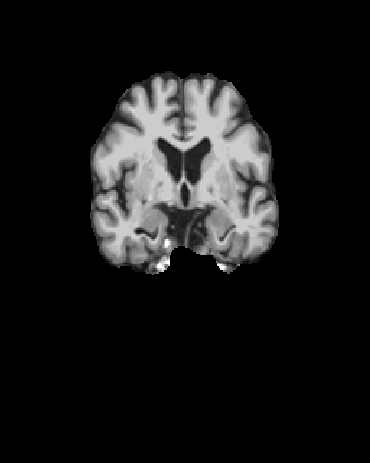

(c) The 52nd axial, 92nd coronal, and 58th sagittal view of the brain extraction outputs from Clinica, which we used for 2D classification.

Furthermore, we extract 2D slices from fixed indices for each view of the spatially normalized brain extraction output. The indices were chosen based on visual prominence of the hippocampus of the brain. Specifically, they were the 52nd slice of axial view, the 58th slice of sagittal view, and the 92nd slice of coronal view. We also experimented with using neighboring slices for classification. Figure 2 shows the 2D slices of the brain extraction output by Clinica.